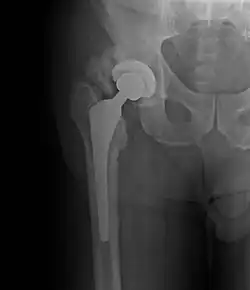

| Heterotopic ossification around the hip joint in a patient who has undergone hip arthroplasty |

Heterotopic ossification of varying severity can be caused by surgery or trauma to the hips and legs. About every third patient who has total hip arthroplasty (joint replacement) or a severe fracture of the long bones of the lower leg will develop heterotopic ossification, but is uncommonly symptomatic. Between 50% and 90% of patients who developed heterotopic ossification following a previous hip arthroplasty will develop additional heterotopic ossification.